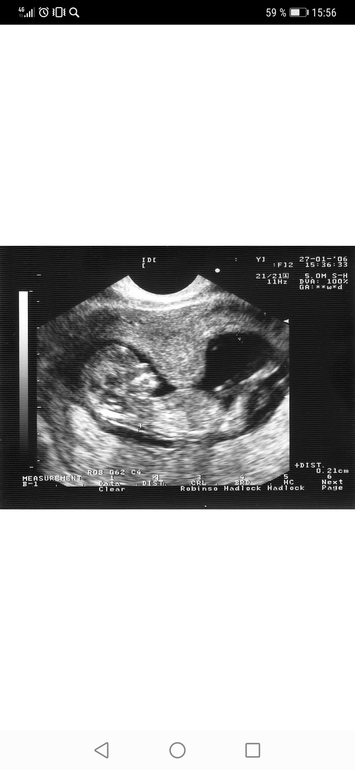

Смотря какой срок, на раннем сроке, у меня тянет при тонусе, и твердеет живот, УЗИ на фото не моё, но у меня был такой-же бугорок

Тянет и каменеет живот, на узи тоже видно, там пространство где находится малыш, дугой

Тянущие боли внизу живота, иногда - как при месячных, иногда - будто напряглась мышца и не может расслабиться. Ну узи сразу видно, какая именно стенка в гипертонусе